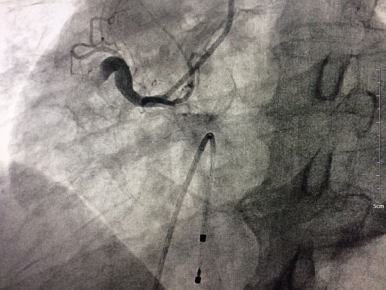

術(shù)前右冠動脈近段完全閉塞

????手術(shù)臺上,老人心率進(jìn)行性下降到40次/分左右,病情極其危重。心內(nèi)科介入手術(shù)團(tuán)隊(duì)迅速為患者植入心臟臨時起搏器,在臨時起搏器的保護(hù)下,醫(yī)生從血管穿刺開始僅耗時15分鐘就完成了冠脈造影術(shù),但檢查結(jié)果十分不樂觀:右冠狀動脈自近端完全閉塞,可見血栓影,袁小蓉立即采用特殊的藥物替羅非班注射液10ml在冠脈內(nèi)推注。在數(shù)分鐘內(nèi),醫(yī)生迅速、準(zhǔn)確的為將導(dǎo)絲通過閉塞段,采用血栓抽吸導(dǎo)管進(jìn)行血栓抽吸,植入支架,打通右冠狀動脈血管,手術(shù)成功了!

術(shù)后右冠動脈近端完全開通